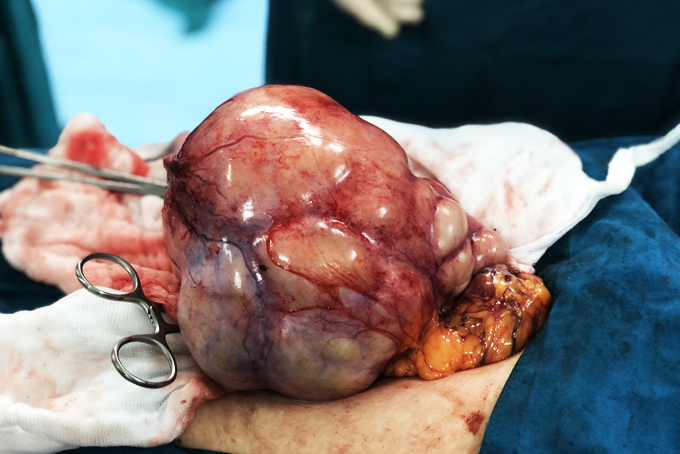

Ê-kíp bác sĩ Bệnh viện 22-12 phẫu thuật lấy khối u quái cho bệnh nhân. |

Trước đó, ngày 4-11, Bệnh viện 22-12 tiếp nhận bệnh nhân T. trong tình trạng vùng bụng dưới có khối to lên bất thường, đau tức vùng bụng. Kết quả siêu âm phát hiện bệnh nhân có khối u ổ bụng vùng hạ vị kích thước to khoảng 20cm. Từ hình ảnh chụp CT ổ bụng và MRI, cùng với thăm khám toàn diện, bệnh nhân T. được chẩn đoán mắc u quái buồng trứng kích thước lớn và được chỉ định phẫu thuật lấy khối u. Ê-kíp ngoại sản do bác sĩ chuyên khoa I Đoàn Thanh Giang, bác sĩ chuyên khoa I Hoàng Ngọc Sơn và bác sĩ Nguyễn Minh Luân tiến hành phẫu thuật mở bụng cắt khối u cho bệnh nhân.

Đây là ca phẫu thuật khó do khối u lớn choán chỗ toàn bộ ổ bụng dưới, khối u có nhiều thùy, sản sinh nhiều mạch máu. Ê-kíp bác sĩ phẫu thuật nhận định khối u có thể đã tự vỡ các thùy vài lần nên các tổ chức xung quanh đến bao bọc và dính vào khối u. Sau khoảng 2 giờ 30 phút, các bác sĩ đã gỡ dính, cắt bỏ thành công khối u kích thước 16x11x15cm (nặng khoảng 2kg). Khối u khi bóc tách ra có chứa nhiều dịch xanh sệt, nhiều mô mỡ, lông, tóc, móng, xương và răng.